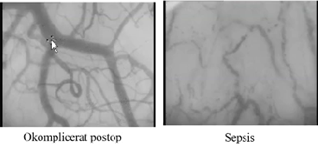

**Anne, 56 år** * Tidigare rökare, annars väsentligen frisk * Inkommer för elektiv partiell mastektomi * Okomplicerat anestesi/kirurgi hem samma dag * Nästa dag – ont i magen, diarré, illamående, kräkning och feber * Tre dagar senare * Feber illamående, ont i hela kroppen * Fysiologiska parametrar: temp 37 grader, högt afterload, väloxygenerad, BT60&30, kallt perifert, spontanandning laktat 9, RLS1 * Lab CRP 654, vita 2,9, Krea 400, koag 78/1,9, 135 Inlagd på IVA, diagnos?

* SEPSIS

27

**Anne, 56 år** * Tidigare rökare, annars väsentligen frisk * Inkommer för elektiv partiell mastektomi * Okomplicerat anestesi/kirurgi hem samma dag * Nästa dag – ont i magen, diarré, illamående, kräkning och feber * Tre dagar senare * Feber illamående, ont i hela kroppen * Fysiologiska parametrar: temp 37 grader, högt afterload, väloxygenerad, BT60&30, kallt perifert, spontanandning laktat 9, RLS1 * Lab CRP 654, vita 2,9, Krea 400, koag 78/1,9, 135 * Inlagd på IVA, diagnos? * SEPSIS Åtgärder?

* Iv antibiotika (bredspektrum initialt, PipTaz) * Odla! * Vätska (kristaloider) – Ringer! * Vassopresin (om de inte svarar på vätska) * Ibland blod

28

**Anne, 56 år** * Tidigare rökare, annars väsentligen frisk * Inkommer för elektiv partiell mastektomi * Okomplicerat anestesi/kirurgi hem samma dag * Nästa dag – ont i magen, diarré, illamående, kräkning och feber * Tre dagar senare * Feber illamående, ont i hela kroppen * Fysiologiska parametrar: temp 37 grader, högt afterload, väloxygenerad, BT60/30, kallt perifert, spontanandning laktat 9, RLS1 * Lab CRP 654, vita 2,9, Krea 400, koag 78/1,9, 135 * Inlagd på IVA, diagnos? * SEPSIS * Åtgärder * Vätska, antibiotika, blododling, vassopressor insatt Dag 4 fick hon petekier på fötterna, vad har hänt?

* DIC (disseminerad intravaskulär koagulation) – mikrotrombotiska komplikationer * **Interaktion mellan inflammation och koagulation** * PK-INR och APTT är högt, * **Hon har chock trots normal puls, CO och laktat** (inget återflöde av laktat eftersom kärlen pluggas)